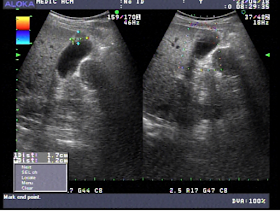

In May to July 2022 he goes to Medic Can tho and then Medic Hoa Hao Center in HCMC.

An coronary CTA of this second time shows slight stenosis under 30% and slight pericardial effusion but notes a hypertrophic cardiomyopathy of his heart.

At last Cardiac MRI confirms an asymmetrical hypertrophy of the heart.